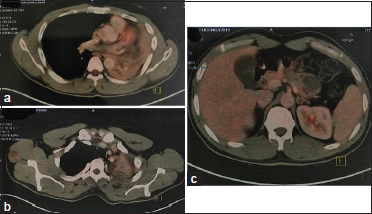

An otherwise well, 34-year-old male with no history of tobacco addiction presented with hemoptysis, intermittent fever, and significant weight loss for 1 year. Examination revealed a 5 cm × 4 cm right axillary lymph node and decreased breath sounds over the left upper lung region, apart from which no other abnormality was detected. Contrast-enhanced computed tomography (CT) of the thorax showed a large neoplasm adjacent to bifurcation of the left main bronchus causing complete collapse of the left lung [Figure 1]. CT-guided biopsy from the lung mass was done for histopathological examination (HPE), which showed features of high-grade myxoid liposarcoma [Figure 2]a] and [Figure 2]b]. Tumor cells were positive for S100 and Ki 67 was 15%. 18 F-fluorodeoxyglucose (FDG) positron emission tomography (PET)-CT scan revealed a mild hypermetabolic predominantly hypodense cystic lesion seen involving the left lung upper lobe inferiorly extending up to the left hilar region, causing abrupt cut-off of main bronchus and encasing upper and lower lobe bronchi causing distal complete collapse consolidation of the left lung upper and lower lobes [Figure 3]a]. Mildly FDG-avid metastatic sites included bilateral axillary lymph nodes, right latissimus dorsi muscle, and hypodense cystic lesion involving pancreas [Figure 3]b] and [Figure 3]c]. In lieu of widely metastatic disease, he was started on palliative chemotherapy with MAID regimen consisting of MESNA, adriamycin, ifosfamide, and dacarbazine chemotherapeutic agents.

| Figure. 3 (a) Fluorodeoxyglucose positron emission tomography-computed tomography scan revealed a mild hypermetabolic predominantly hypodense cystic lesion seen involving the left lung upper lobe, (b) Mildly fluorodeoxyglucose avid metastatic deposit is seen in the right latissimus dorsi muscle and (c) Mildly fluorodeoxyglucose-avid hypodense cystic lesion involving pancreas